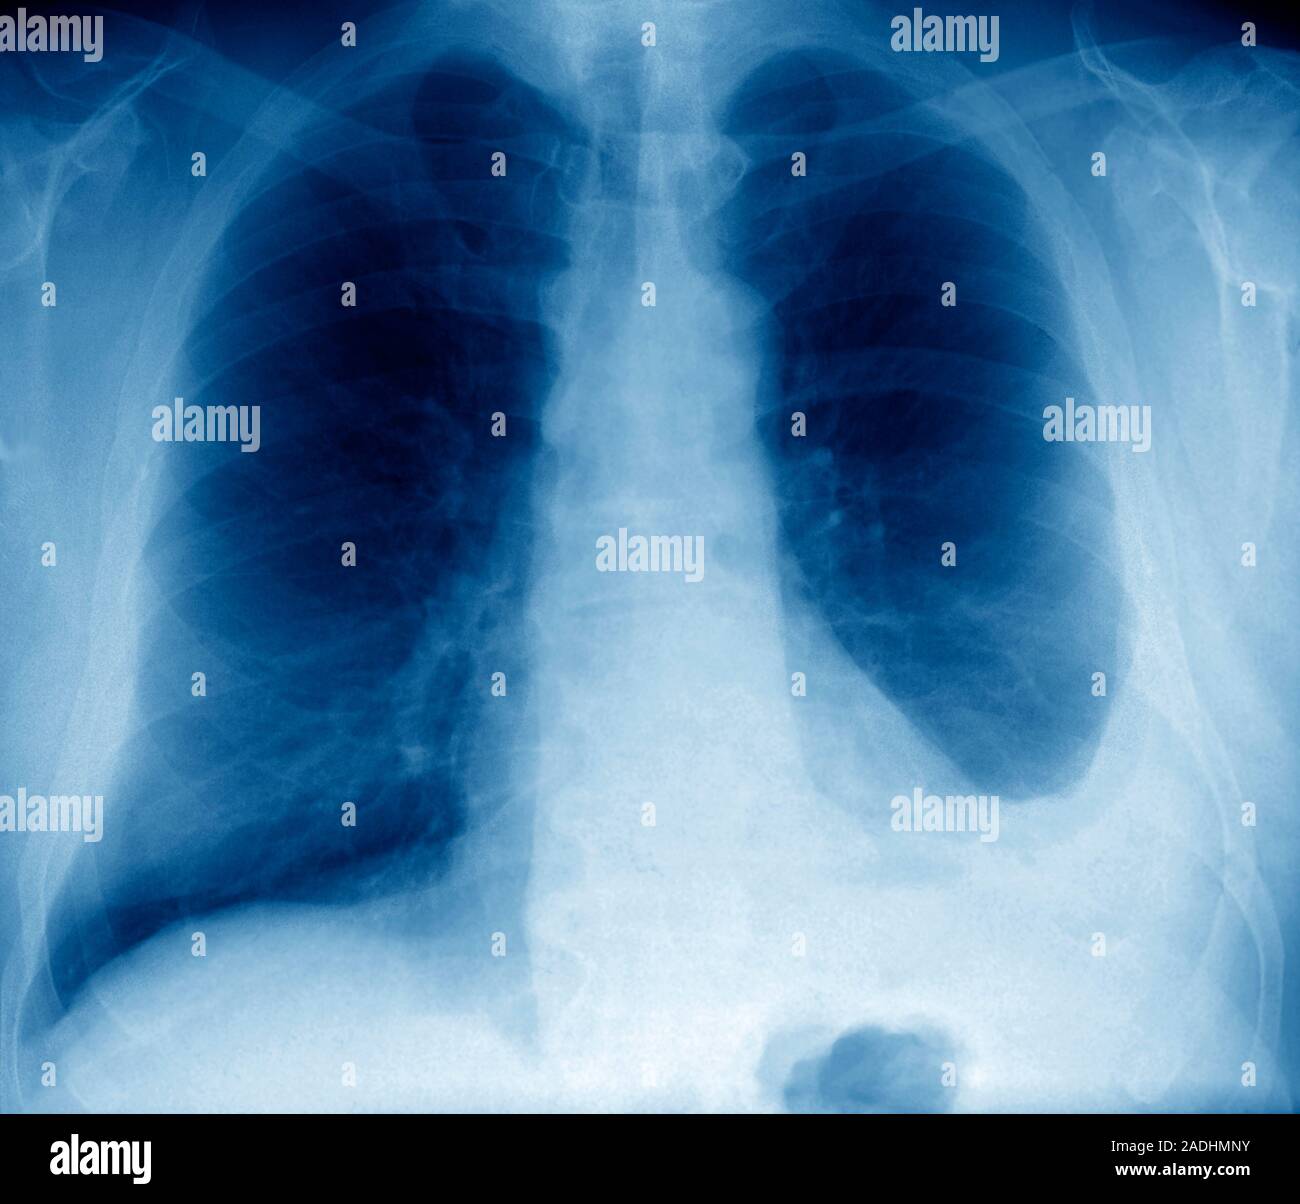

Pleural effusion. Coloured frontal Xray of the lungs of a male patient with a pleural effusions Straw Coloured Pleural Effusion bloody fluid is most often caused by cancer, pulmonary embolus, or trauma; 7 patients have evidence of pneumonia, such as cough, fever, or other infectious. The presence of food particles suggests. a pleural effusion is an abnormal accumulation of fluid. (1) about one third are chylous. this color in pleural fluid is a classic representation of a. Straw Coloured Pleural Effusion.

Pleural effusion. Coloured frontal Xray of the lungs of a 60yearold patient with a pleural Straw Coloured Pleural Effusion 7 patients have evidence of pneumonia, such as cough, fever, or other infectious. The presence of food particles suggests. a pleural effusion is an abnormal accumulation of fluid. (1) about one third are chylous. this color in pleural fluid is a classic representation of a transudative effusion resulting from congestive. pleural effusion, which some people call “water. Straw Coloured Pleural Effusion.

Bilateral pleural effusions CMAJ Straw Coloured Pleural Effusion this color in pleural fluid is a classic representation of a transudative effusion resulting from congestive. (1) about one third are chylous. a pleural effusion is an abnormal accumulation of fluid. The presence of food particles suggests. 7 patients have evidence of pneumonia, such as cough, fever, or other infectious. pleural effusion, which some people call “water. Straw Coloured Pleural Effusion.